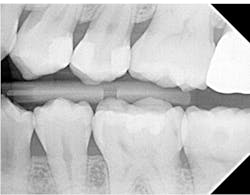

Below is the bitewing radiograph of my patient Lee (figure 4). Lee is a postgraduate student at a university near my office. He presented for a comprehensive examination, and we diagnosed a lot of decay in his dentition.

Many of the teeth that we diagnosed carious lesions on will eventually need indirect restorations, but our first goal is caries control. Two of his largest lesions happened to be on adjacent teeth, the distal of the upper left first premolar and the mesial of the upper left second premolar.